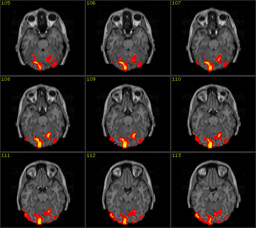

The automatism and, at the same time,

ineffability of thinking can be put into an image thanks to progresses in

neuroscience and biomedical techniques of image formation and visualization.

The illustration shows two images: the first one is a scan of the brain

obtained with Magnetic Resonance Imaging (MRI), the second is its functional

version (fMRI). MRI is a non-invasive scientific technique that generates

images of the body for diagnostic and research purposes. Along with its

functional version, MRI has been extensively applied to studies of brain

anatomy and cognitive functions, enabling researchers to detect and measure

the neuronal activity in almost real time. By showing the human brain at work,

brain scans are presented in the wider public arena and, specially, in the

media, as evidence of conditions of normality or illness that prompt us to

reshape our concept of personal identity (Dumit 2004).14

Brain scans embody both image traditions

that historian of science Peter Galison individuated within the field of

physics: the first tradition, called logical, substitutes the notion of the

image with the notion of statistical projection of data and digital

information; the second tradition, called image, describes images as natural,

illusionary or mimetic. According to this second tradition, images ‘preserve the form of things as

they occur in the world’ (Galison, 1997, 807). Brain scans function as authoritative

visual objects that are part of a multi-layered ensemble of networked

techniques and technologies (both analogical and digital) and human mediations,

embodying the logic of the database (de Rijcke and Beaulieu, 2014) and being

more the statistical projections of data rather than representations.

Therefore, brain scans can be aptly called image-data.

Experts in the laboratory do not always need to see the image because they are capable of reading it in accordance with the aforementioned logical tradition. Non-experts, on the contrary, can interpret the brain scan only as an image belonging to the second tradition. Both strategies, reading and seeing, however, are made possible thanks to notions that belong to art history and practice such as perspective, background and foreground, chiaroscuro, intensity, orientation, composition, colour grading, etc, and by bearing upon the cultural history of the representations of the brain from Leonardo, Vesalius through phrenology and recent brain imaging techniques. Already at a production stage brain scans are created by referring to the cultural background, concepts and techniques that belong to the art field as Elkins highlights: ‘the images cannot be produced without drawing on the longer history of mimetic art. For that reason they also cannot be fully interpreted without fully tracing the effects of modern and pre-modern pictures…they are art images in disguise’ (Elkins, 2008: 173). This double belonging of brain images to the scientific and the artistic field is in tune with de Rijcke and Beaulieu’s understanding of brain scans as boundary objects between disciplines (de Rijcke and Beaulieu, 2014: 131) and with our attempt to discuss brain scans along with an image coming from experimental cinema.

This series of images can be seen but cannot be read without knowing the language of neuroscience and of brain anatomy and physiology. For the purpose of this essay, it is not worthwhile going into details on how brain scans are produced, re-mediated and interpreted inside and outside the laboratory. Therefore, I shall not discuss the scholarly literature (de Rijcke and Beaulieu, 2014; Prasad, 2005; Alac, 2008; Dumit, 2004 to name just a few) that shows how brain images are the result of complex socio, technical and semiotic procedures of mediations and interpretation taking place inside the laboratory and among different professionals.